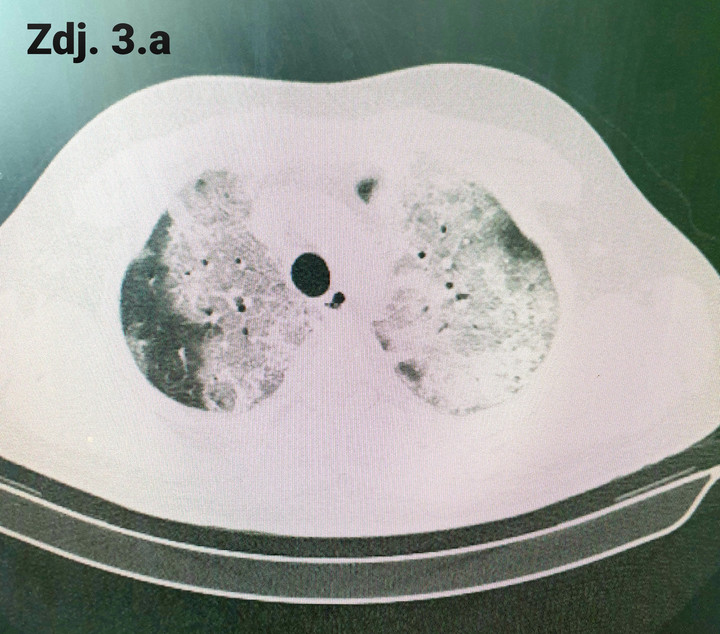

To może przypadek młodego antycovidowca, który trafił do szpitala mniej więcej po tygodniu od wystąpienia objawów. Miał 25 lat, nie był obciążany, żadnymi chorobami, o których by wiedział, co nie znaczy, że nie miał jakichś genetycznych uwarunkowań. Generalnie na pierwszy rzut oka normalny gość. Oczywiście jak to osoba młoda i zbuntowana bagatelizował pierwsze objawy infekcji, rzucał się w wir spotkań towarzyskich, głośno mówiąc, że nie wolno dać się zamknąć „plandemii”. Żył chwilą, ale chwilę potem, kiedy dziwne wrażenie w piersiach zaczęło się nasilać, a dreszczyk emocji wynikający z bycia „rebelem” zniknął, z tyłu głowy pojawiła się u niego obawa. To co najpierw było małym kamyczkiem na klatce piersiowej, stopniowo stawało się wielkim głazem, który leżał na piersiach i nie pozwalał oddychać. Tak działa koronawirus, kradnie nam powietrze, dosłownie kradnie, bo efektywna powierzchnia wymiany gazowej w płucach stopniowo się zmniejsza. Miąższ płuc zalewa mieszanina komórek zapalnych i wysiękającego płynu pozakomórkowego, naszpikowanego szeregiem substancji, tzw. cytokin, które dodatkowo przyprawiają szalejący stan zapalny. Obrazowo można przyrównać płuca do gotującej się zupy. I taki obraz rozhukanego stanu zapalnego obserwujemy na zdjęciach rentgenowskich oraz obrazach tomografii komputerowej, fachowo nazywamy go mleczną szybą. Dla przykładu, na zdj. nr 2 widać obraz prawidłowych płuc. Wszystkie czarne przestrzenie to upowietrzniona, zdrowa tkanka płucna. Promieniowanie X przechodzi przez powietrze bez oporu, nie jest pochłaniane, natomiast każda przeszkoda na jego drodze, czyli te wszystkie komórki zatopione w płynie zapalnym, w pewnym stopniu je pochłaniają, rzucając swoisty cień na obraz zdrowych płuc. Możemy to obserwować jako jasne przebarwienia, które do złudzenia przypominają mleczne, jakby oszronione szkło. Zagranicą stosuje się określenie „frosty glass” i bardzo dobrze widać je na zdjęciu nr 1. Żeby ocenić, ile procent miąższu płucnego jest zajętych zmianami zapalnymi, musimy skorzystać z obrazowania wielopłaszczyznowego, czyli

Zdjęcie nr 1

Na zdjęciu nr 3 a i b widzimy przekrój przez klatkę piersiową, uzyskany za pomocą tej metody obrazowania. Zdjęcia pokazują zakres zmian śródmiąższowych, czyli te wszystkie białe jakby rozlane plamy u jednego pacjenta. Oceniamy je na różnych wysokościach płuc, tutaj na zdjęciu 3a na wysokości szczytów płuc (tuż poniżej ramion) i na poziomie serca (zdj. 3b). Procentowa zawartość zdrowego (czarnego) miąższu jest niewielka. Oczywiście w większości przypadków zmiany w toku leczenia zmniejszają się, a obraz płuc ulega uporządkowaniu, ale ten proces wymaga czasu. Ile? Na tą chwilę, nie mamy jeszcze długoterminowych, opartych na dużej liczbie przypadków badań, które pokazałyby, jak długo i w jakim stopniu organizm będzie wracał do pierwotnego stanu i czy w ogóle wróci.

Zdjęcie 3a

Zdjęcie 3b